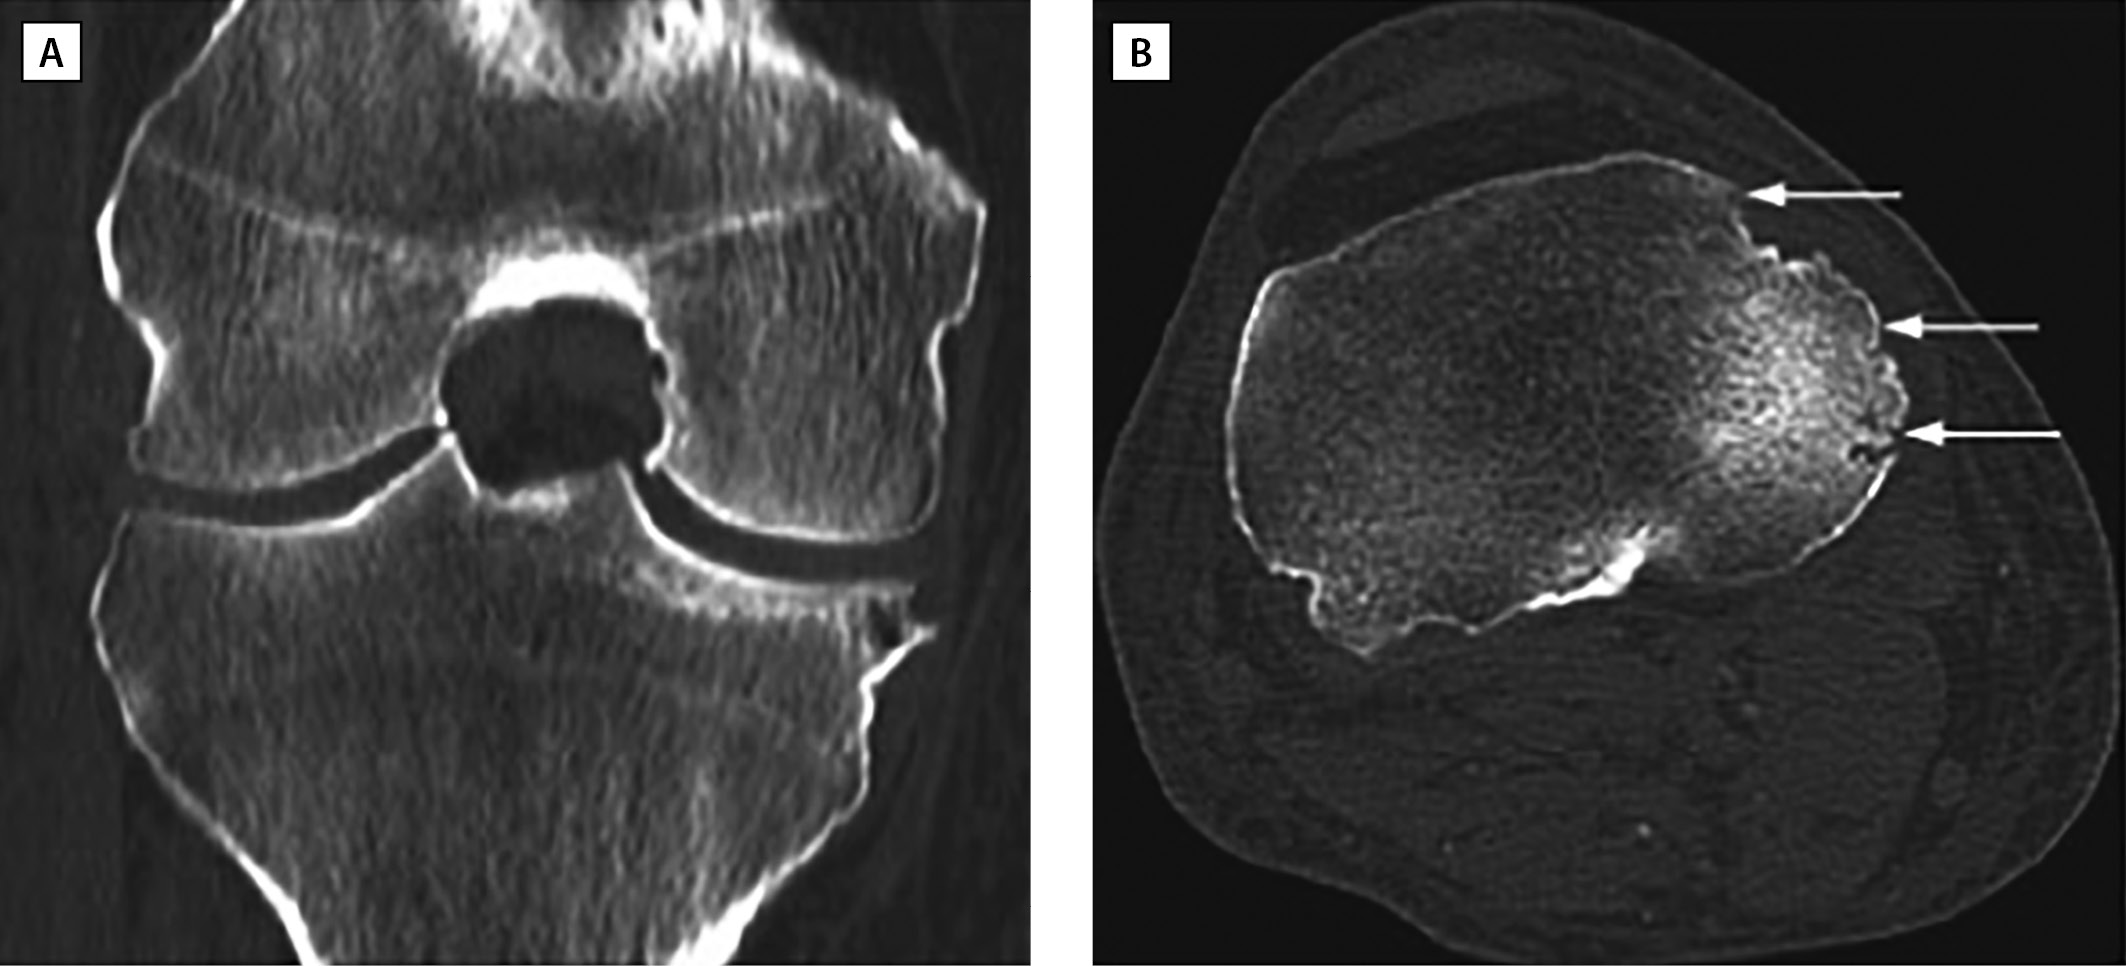

Например, S. Chatterjee и соавт. [64] описали клинический случай пациента 67 лет, страдающего хронической тофусной подагрой более 30 лет. На момент осмотра пациент предъявлял жалобы на артрит правого коленного сустава с типичными для подагры характеристиками. Назначенная 6 мес назад УСТ (аллопуринол 100 мг/сут) не привела к нормоурикемии (МК сыворотки — 410 мкмоль/л). Однако увеличение дозы препарата до 200 мг/сут в отдаленной перспективе способствовало не только снижению частоты и интенсивности приступов, но и рассасыванию, в том числе, «внутрикостных» тофусов, обнаруженных на КТ, проявляющемуся в уменьшении числа и размеров костных эрозий (рис. 2, 3).

Рисунок 2. КТ правого колена пациента с хронической тофусной подагрой при поступлении (адаптировано из Chatterjee S. и соавт., 2008) [64].

(A) Тофусные отложения (белые стрелки) в коленном суставе, прилегающие к медиальной и латеральной коллатеральным связкам и межмыщелковой вырезке. Выраженная эрозия на медиальном мыщелке большеберцовой кости (черная стрелка).

(В) Тофусные отложения вдоль медиальной и латеральной сторон коленного сустава (большие стрелки) и эрозии мыщелка большеберцовой кости (маленькие стрелки).

Figure 2. CT scan of the right knee of a patient with chronic tophi gout on admission (adapted from Chatterjee S. et al., 2008) [64].

(A) Tophi deposits (white arrows) in the knee joint adjacent to the medial and lateral collateral ligaments and intercondylar notch. Severe erosion on the medial tibial condyle (black arrow).

(B) Tophi deposits along the medial and lateral sides of the knee joint (large arrows) and erosion of the tibial condyle (small arrows).